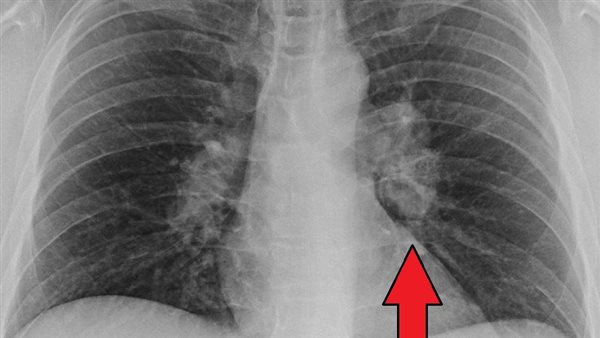

وللإجابة عن سؤال هل الساركويد مرض مناعي؟، تؤكد أخصائي أمراض الروماتيزم والمناعة، أن داء الساركويد يعد أحد الأمراض المناعية غير معروفة السبب، وعادة ما يظهر على شكل مجموعات غير طبيعية من الخلايا الالتهابية "الحبيبية " والتي قد تكون عقيدات في عدة أعضاء بالجسم، لافتة إلى أن الهجمهات الحبيبية في أغلب الحالات تحدث بالرئتين والعقد اللمفاوية المرتبطة بها، في حين أنه من الوارد أن يصاب بها أيضًا أي عضو آخر، وعادة ما تظهر أعراضه بشكل تدريجي ولكن في بعض الحالات قد تظهر بشكل مفاجىء.

وتنبه إلى أن حوالي 60٪ من المرضى لا تظهر عليهم أي أعراض، ولكن يتم اكتشاف الساركويد لديهم عن طريق الصدفة، ويكون ذلك في أغلب الحالات عقب إجراء تصوير للصدر لسبب آخر، موضحة أنه من أبرز أعراض الساركويد ما يلي: